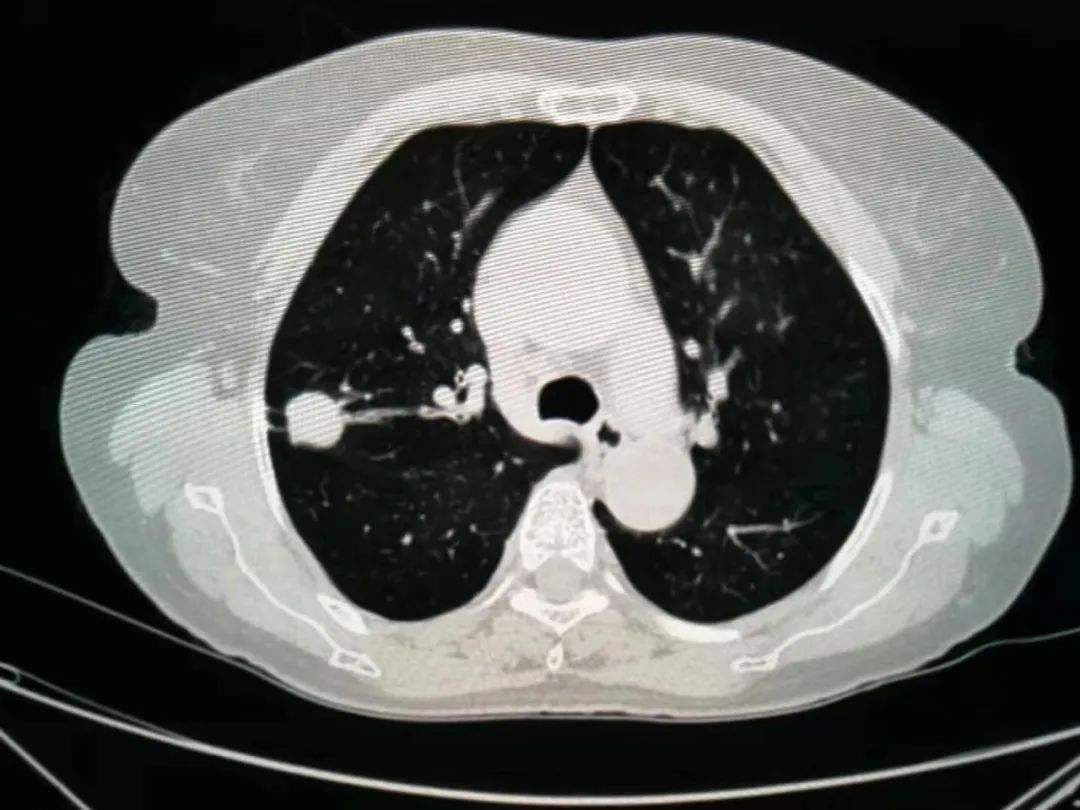

前不久,69岁的李奶奶在体检时发现“右肺上叶占位性病变2周”,家人赶忙为李奶奶办理了住院手续。据李奶奶的主管医师王刚介绍:“老人来院时,胸部CT显示右肺上叶占位性病变,位于后段,大小约2.0×1.8cm,边缘见毛刺及分叶,邻近胸膜略增厚、牵拉,属于发现比较及时的早期肺癌。”

我院胸外科团队经过充分讨论后,考虑患者年龄偏大,肺功能较差,为减少手术创伤,避免行肺叶切除后肺功能损失多,决定给予实施“单操作孔胸腔镜下右上肺S2+3a亚段切除加特异性淋巴结清扫术”。